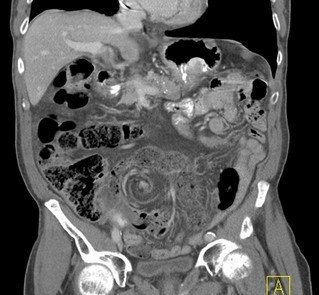

Abdominal CT images

Large gas-filled loop without haustral markings, forming a closed-loop obstruction

Beak sign: Progressive tapering of afferent and efferent limbs leading into twist